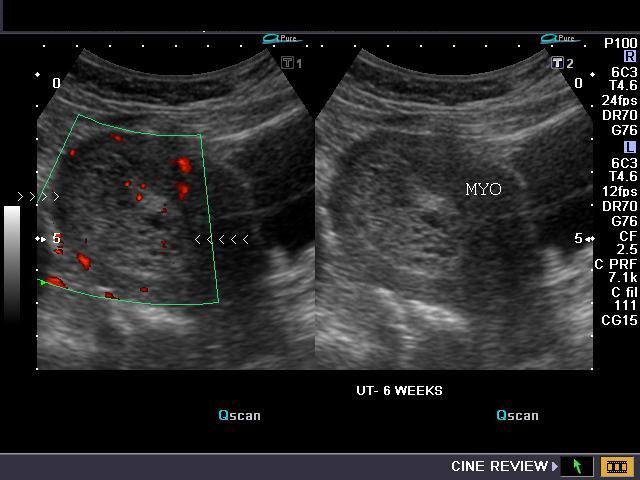

This is a case of a female patient presenting with a history of 5 weeks of amenorrhoea and scanty bleeding. She was sent for diagnostic ultrasound imaging.

Our patient presents with a history of 5 weeks of amenorrhoea and scanty bleeding per vagina. Based on her history and ultrasound images, what is your diagnosis?